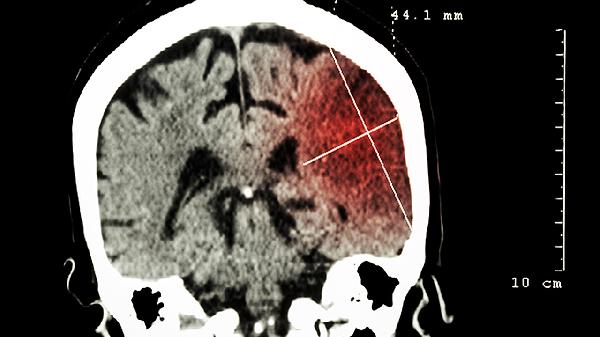

北京修补颅骨钛网和peek哪个好

颅骨修补手术中,钛网和PEEK材料各有优劣,选择需根据患者具体情况决定。钛网价格较低,生物相容性好,但可能出现排异反应;PEEK材料更接近颅骨硬度,外观更自然,但成本较高。